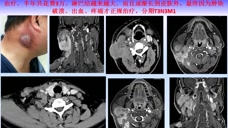

鼻咽癌確診後主要的治療手段是放療,早期單純放療,中晚期放化療。我們邀請復旦大學附屬腫瘤醫院放射治療中心的王孝深教授通過大量病人的實例,結合自己豐富的工作經驗。用通俗易懂,生動有趣的語言,為鼻咽癌的早期發現和早期診斷,進行了精彩的講述。王教授總結道:對於鼻咽癌引起的癥狀,病人自身的警惕很重要;非腫瘤科醫生要知曉鼻咽癌的相關知識;磁共振MRI對於鼻咽腫瘤的顯示至關重要;高科技技術要掌握,但簡單、傳統的技術不能丟棄。本講座適合健康人群科普學習,也適合相關醫務人員加深對鼻咽癌的了解,對患者進行宣教使用。歡迎收看交流!